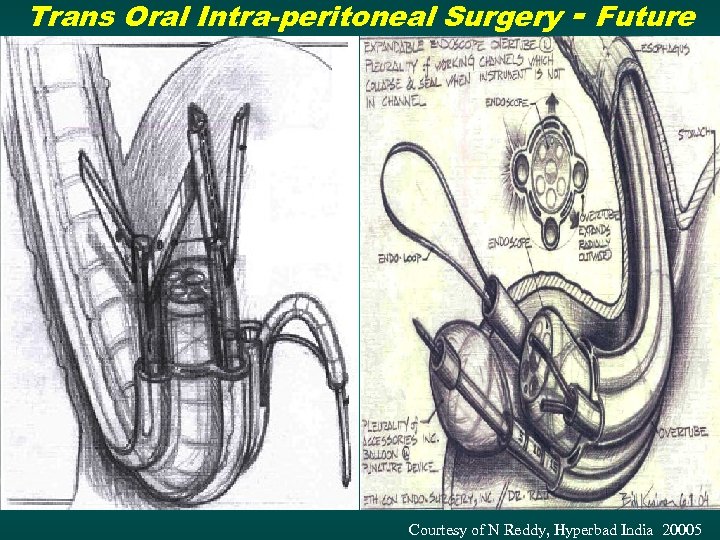

Trans Oral Intra-peritoneal Surgery - Future Courtesy of N Reddy, Hyperbad India 20005

Trans Oral Intra-peritoneal Surgery - Future Courtesy of N Reddy, Hyperbad India 20005